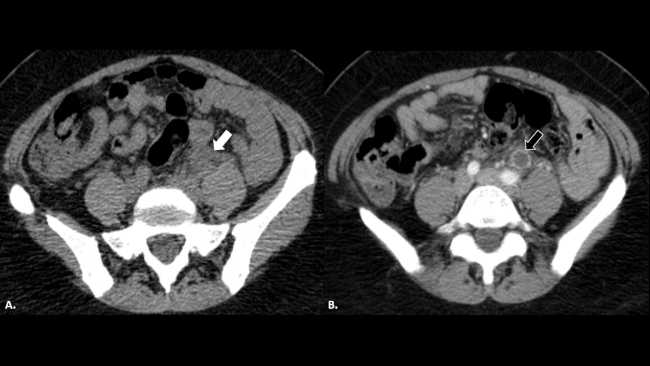

Tiempo atrás, la enfermedad ureteral era estudiada con radiología convencional por ureteropielografía ascendente, mientras que en la actualidad la ecografía, tomografía computada (TC) o resonancia magnética (RM) la han reemplazado y a pesar de no mostrar el reflujo ureteral de forma dinámica, evalúan de mejor manera sus complicaciones. Hoy en día, el diagnóstico tiende a ser más precoz, aun cuando la enfermedad no es inicialmente sospechada, debido al amplio uso de la TC para patología abdominal de guardia (►Fig. 1). Por lo tanto, conocer los hallazgos imagenológicos y las opciones terapéuticas contribuye al manejo de una enfermedad poco conocida.

Paciente con nefrectomía izquierda por infección del tracto urinario (ITU) y litiasis a repetición. TC de abdomen sin contraste en corte axial (a) donde se reconoce proceso inflamatorio retroperitoneal izquierdo, de difícil caracterización (flecha blanca). TC de abdomen con contraste endovenoso en corte axial (b) que muestra una estructura tubular dilatada retroperitoneal izquierda, con refuerzo de sus paredes y cambios inflamatorios regionales, compatible con empiema del muñón ureteral (flecha negra).

La TC con contraste endovenoso es por amplio margen la mejor técnica para el diagnóstico del EMU. Se trata de un estudio rápido, con alta sensibilidad y especificidad, que nos permite (►Fig. 2) no solo demostrar la existencia de un EMU visible como una estructura tubular dilatada en el trayecto del uréter remanente, con refuerzo y engrosamiento de su pared, sino que también nos ayuda a evaluar las posibles causas del mismo (litiasis, compresión extrínseca de la pared del muñón o tumores) y complicaciones como abscesos asociados en peritoneo o en músculo psoas (►Fig. 3).4,5,6,7,8

Reconstrucciones tomográficas en (a) coronal y (b) sagital del caso descripto en la ►Figura 1. Se reconoce la dilatación del uréter remanente con refuerzo de sus paredes a lo largo de todo su trayecto (flechas blancas).